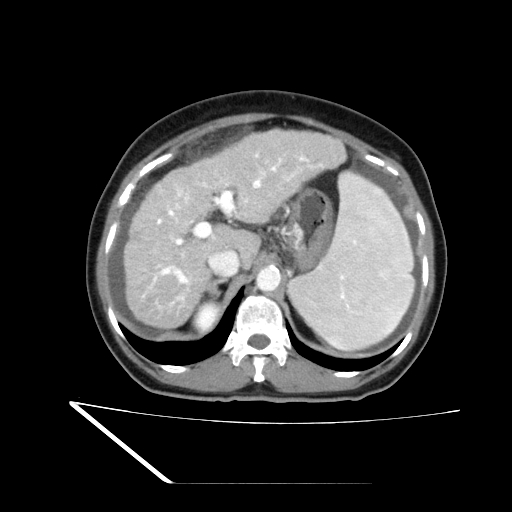

La tomografía multifásica demostró hígado de bordes irregulares, con redistribución del volumen y parénquima levemente heterogéneo, hallazgos compatibles con cirrosis hepática. No se identificaron lesiones focales sospechosas en el momento del estudio.

Se documentaron datos claros de hipertensión portal, caracterizados por dilatación de la vena porta (16 mm), esplenomegalia significativa (volumen aproximado de 800 cc) y dilatación de la vena esplénica. Asimismo, se evidenció líquido libre intraabdominal distribuido en recesos peritoneales, con volumen estimado de 300 cc, compatible con ascitis secundaria a hepatopatía crónica.